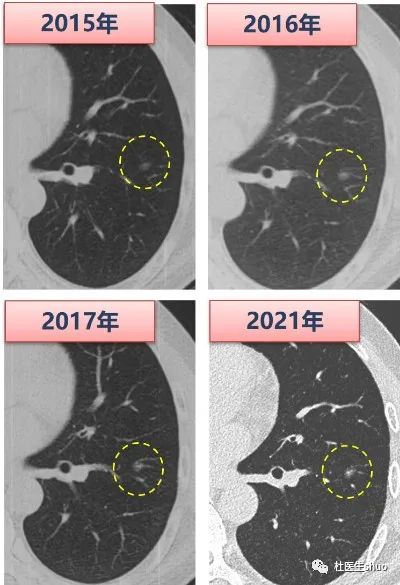

事实上,肺部磨玻璃结节属于惰性病变,发展缓慢,往往呈3至5年增长1至2毫米的“龟速”。这就使得肺部磨玻璃结节患者选择手术的窗口期大为延长。

但是,肺部磨玻璃结节腺癌生长速度、恶性程度的个体差异化原因,至今尚不明确。对于无法辨明病理阶段的结节,建议定期随访观察CT,动态看变化。

肺结节如果有大小、形态、密度的改变,请及时胸外科就诊。